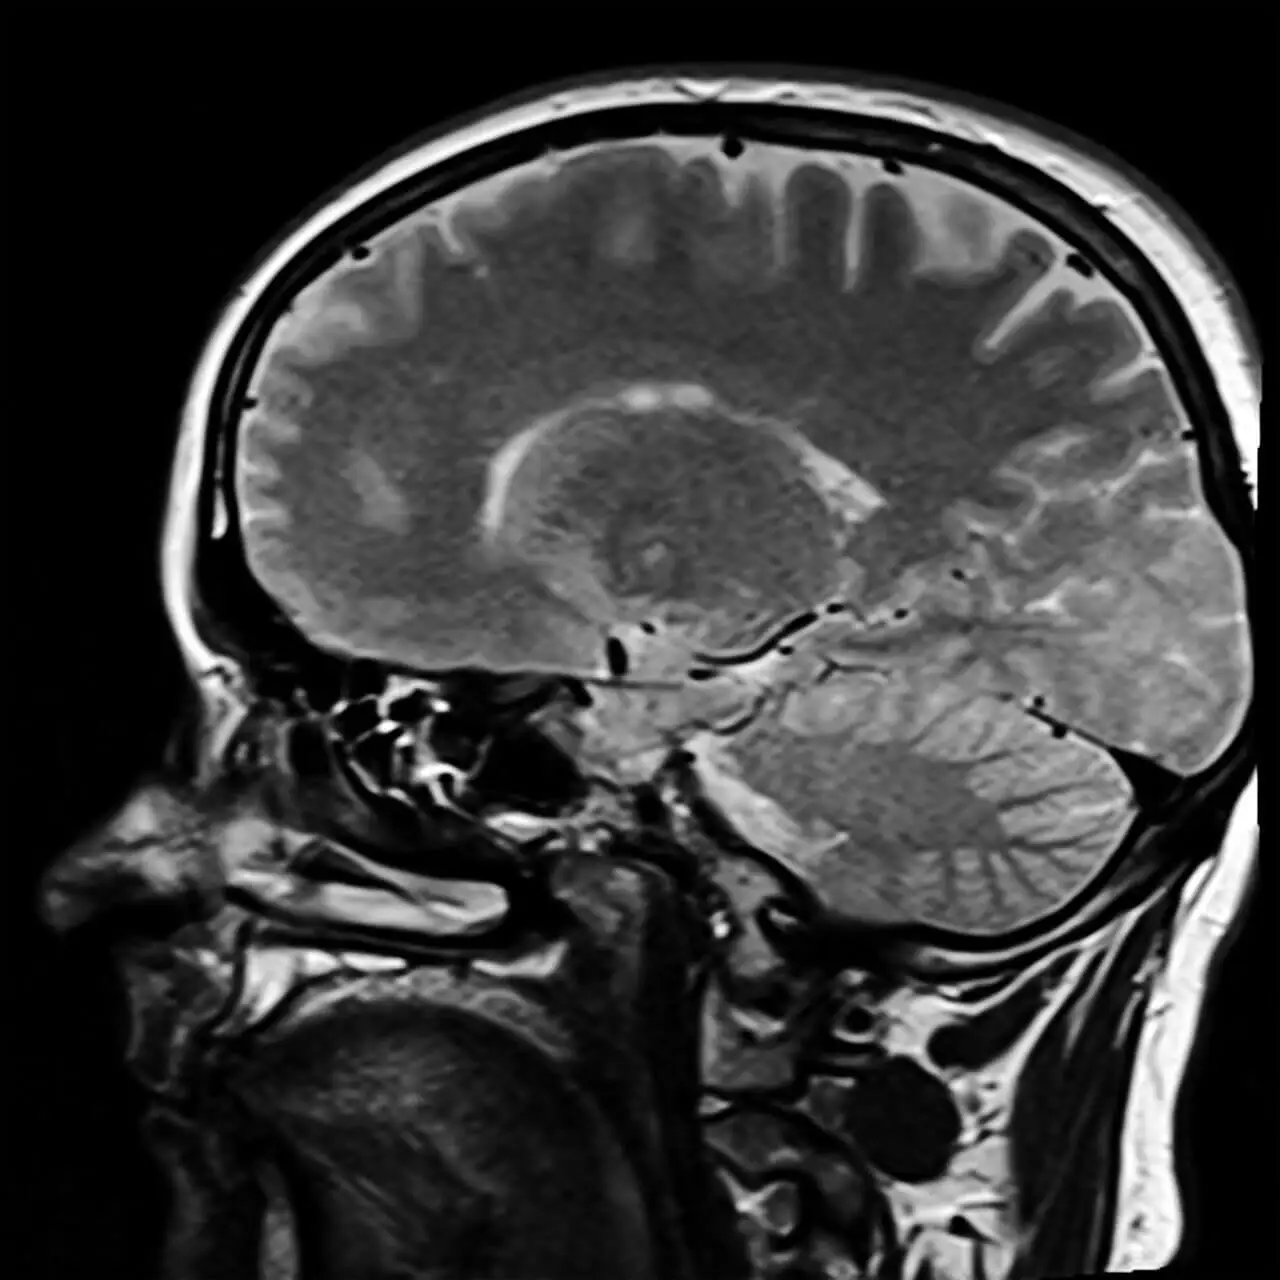

Ψυχοπάθεια: Όταν ο εγκέφαλος είναι διαφορετικός

Έχουμε ήδη μιλήσει για το πώς είναι ένας κοινωνιοπαθής, αλλά τι συμβαίνει στην περίπτωση των ψυχοπαθών; Σε αυτές τις περιπτώσεις, βρίσκουμε ανθρώπους που έχουν διαφορετικό εγκέφαλο.

Ορισμένες έρευνες και μελέτες, όπως αυτή του Diversitas: Perspectivas en Psicología, έχουν καταδείξει αξιοσημείωτες διαφορές στη δομή του εγκεφάλου των ανθρώπων που έχουν διαγνωστεί ως ψυχοπαθείς.

Υπάρχουν επίσης προβλήματα στον προμετωπιαίο φλοιό, γεγονός που καθιστά τον εγκέφαλο διαφορετικό από την πρώτη στιγμή που γεννιέται ένας άνθρωπος. Επομένως, θα μπορούσαμε να πούμε ότι ο ψυχοπαθής γεννιέται- δεν χρειάζεται να περάσει μια τραυματική παιδική ηλικία, αφού ο εγκέφαλός του παρουσιάζει ορισμένα χαρακτηριστικά.

Αυτή είναι η κύρια διαφορά μεταξύ ενός κοινωνιοπαθούς και ενός ψυχοπαθούς.